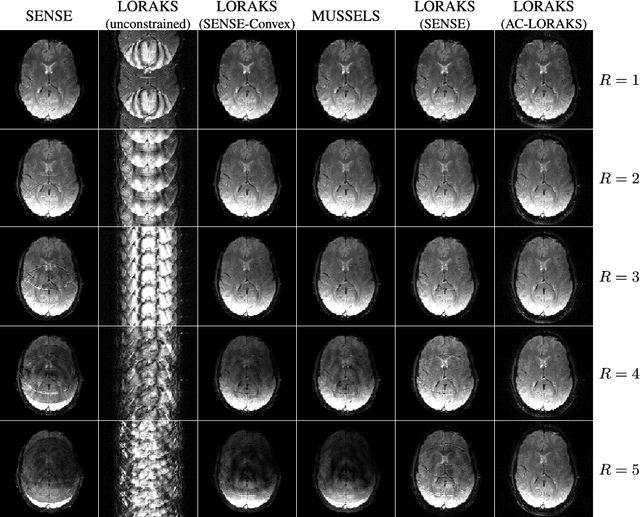

Abstract:Structured low-rank matrix models have previously been introduced to enable calibrationless MR image reconstruction from sub-Nyquist data, and such ideas have recently been extended to enable navigator-free echo-planar imaging (EPI) ghost correction. This paper presents novel theoretical analysis which shows that, because of uniform subsampling, the structured low-rank matrix optimization problems for EPI data will always have either undesirable or non-unique solutions in the absence of additional constraints. This theory leads us to recommend and investigate problem formulations for navigator-free EPI that incorporate side information from either image-domain or k-space domain parallel imaging methods. The importance of using nonconvex low-rank matrix regularization is also identified. We demonstrate using phantom and \emph{in vivo} data that the proposed methods are able to eliminate ghost artifacts for several navigator-free EPI acquisition schemes, obtaining better performance in comparison to state-of-the-art methods across a range of different scenarios. Results are shown for both single-channel acquisition and highly accelerated multi-channel acquisition.